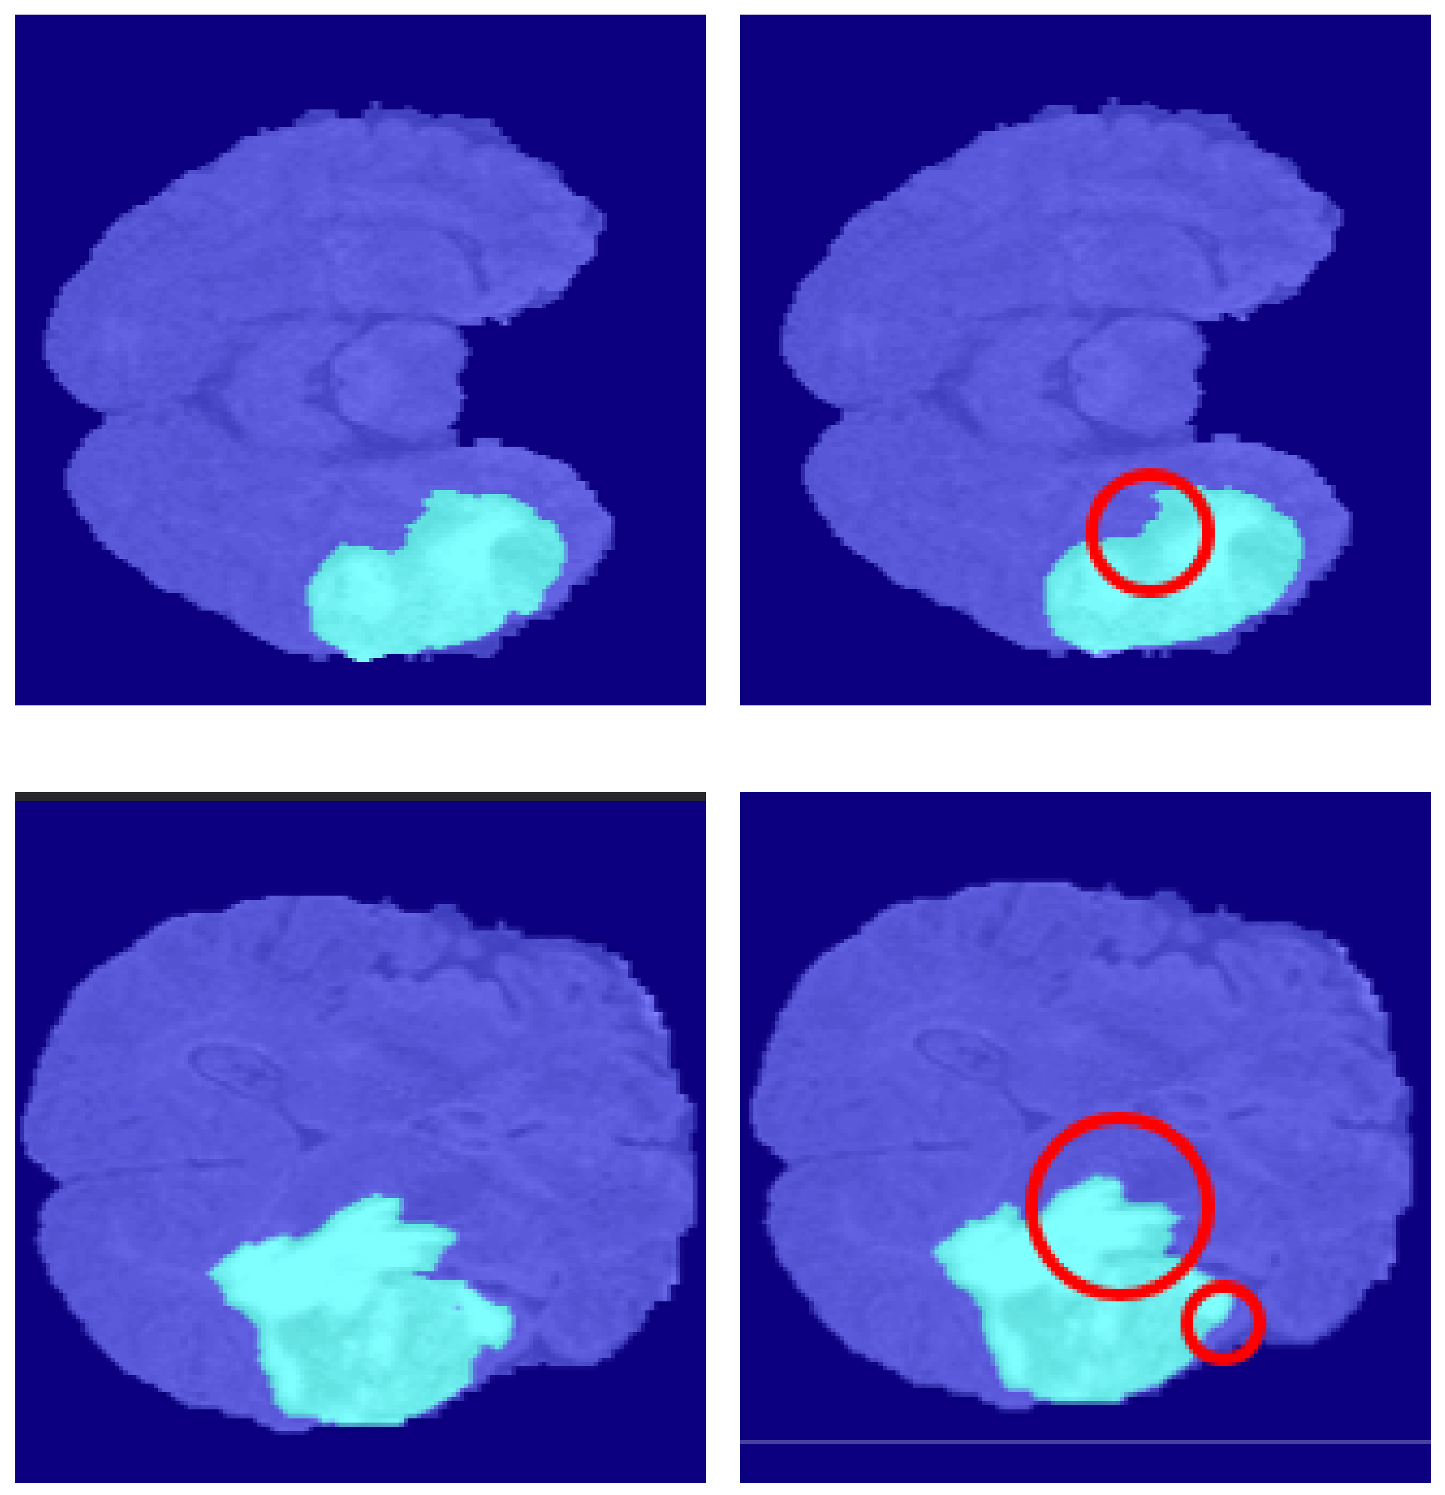

4.2. Segmentation Results

5.6.1. Segmentation Boundary Loss

5.6.2. Third Dimensional Information Loss